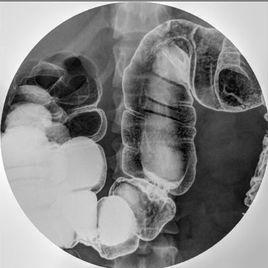

結腸雙對比造影

結腸雙對比造影適用於早期腫瘤和結腸的細小病變(如小息肉、潰瘍性結腸炎的早期病變),觀察結腸黏膜正常微細結構,無名溝的正常和異常改變。

1.患者左側頭低位臥於檢查台上,以灌腸器的壓力經肛管注入鋇劑,繼之令患者順時針轉至俯臥位,於透視下觀察鋇劑行走方向,使鋇液順位流動。鋇劑到達橫結腸脾曲時取右側臥位,待鋇劑自然流入橫結腸肝曲時注氣500~800ml(兒童200~400ml)。

2.投照位置 多體位多角度行全面觀察,按需要及時拍攝點片。拍片應包括大腸的全部。

1.低張狀態下灌注鋇/氣時要本著氣往高處走、鋇往低處流的原則,注意體位的變換,使氣鋇均勻塗布於腸壁,包括回盲部。這是造影成功與否的關鍵。

2.攝片應多變換體位,力求將各腸管分段展開。構成良好的腔壁雙對比像,並分段點片,病變處要求同時點充盈像。